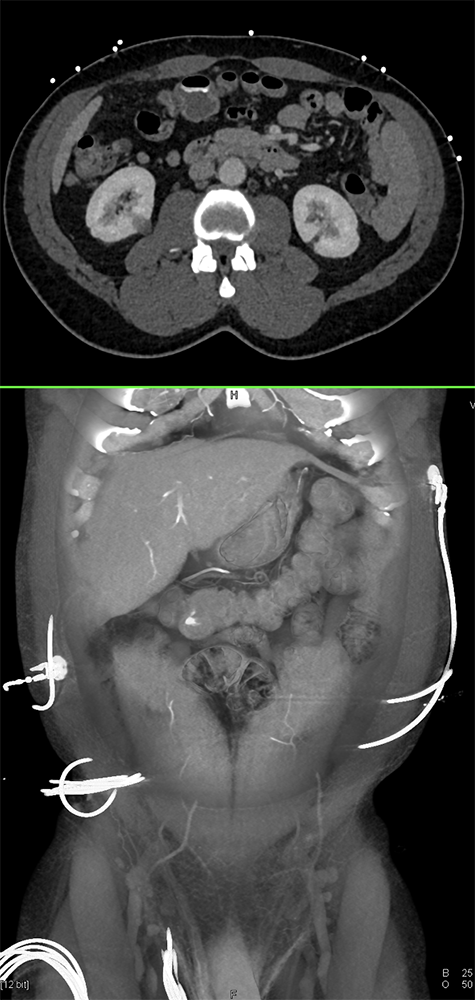

Bleeding Ulcer Small Bowel in Patient with Polymyositis and ILD (Bleed increases Art-Venous) ![]() |

![]() |